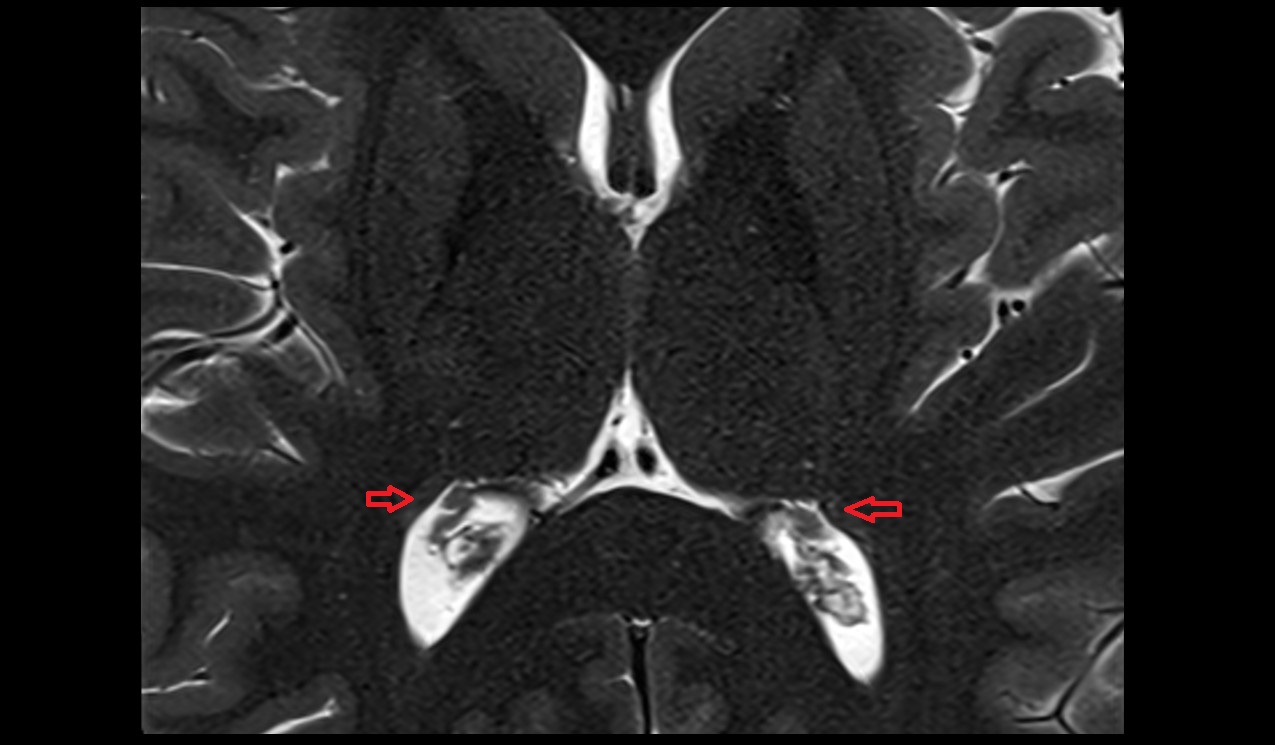

- Cerebellar tonsil (H IX)

- Tonsil of cerebellum